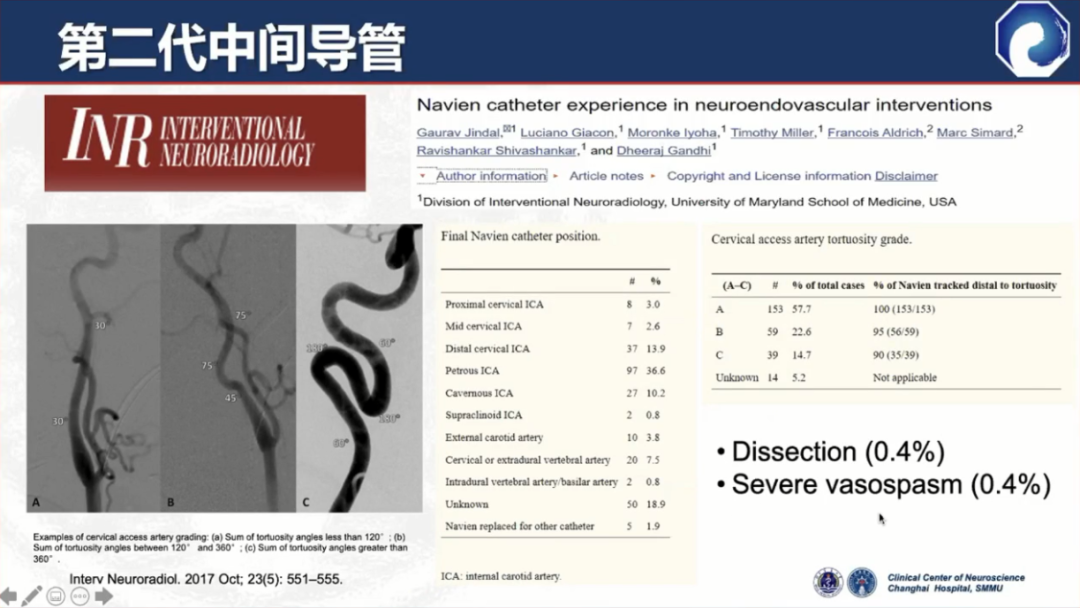

以Navien为代表的第二代中间导管诞生,通过性和到位能力有了显著提升

第二代中间导管仍存在血管内夹层等并发症,这也是所有导管都存在的问题。